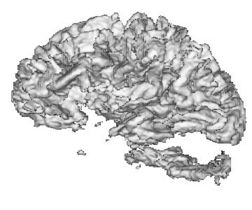

| + | {| | ||

| + | |+ '''Fig 2. EM Segmentation: 3D Rendered Segmentations (1993)''' | ||

| + | |valign="top"|[[Image:four.jpg|thumb|252px|3D view of segmented white matter surface from thresholding]] | ||

| + | |valign="top"|[[Image:five.jpg|thumb|252px|3D view of segmented white matter surface from EM]] | ||

| + | |} | ||

The EM segmener was the first algorithm that could produce high quality segmentations of white matter and gray matter from MRI, with no manual intervention needed on a per case basis. This proved to be very valuable in a large longitudinal study of MS in the period 1994 - 1995.